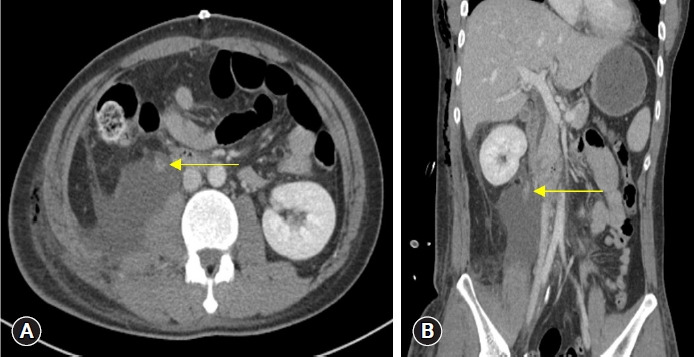

Traumatic ureteral injuries account for fewer than 1% of traumatic urologic injuries, and those caused by blunt trauma are even rarer than those caused by penetrating trauma. The symptoms associated with ureteral injury may be subtle, with or without hematuria, making it difficult to diagnose. We report the case of a 31-year-old man with a delayed diagnosis of proximal ureter injury after abdominal blunt trauma sustained in a motorcycle traffic accident. The patient underwent emergency laparotomy on admission for liver injury, mesenteric injury, and resultant hemoperitoneum. On postoperative day 6, he underwent angioembolization for suspected remnant intra-abdominal bleeding. Persistent symptoms of flank pain and leukocytosis led to follow-up imaging studies that revealed proximal ureter injury, and the patient underwent unilateral nephrectomy. This case stresses the importance of clinical suspicion for genitourinary injuries in the presence of abdominal trauma.

输尿管外伤在泌尿系统外伤中所占比例不到 1%,钝器外伤造成的输尿管外伤比穿透性外伤造成的输尿管外伤更为罕见。输尿管损伤的相关症状可能很隐蔽,伴有或不伴有血尿,因此很难诊断。我们报告了一例因摩托车交通事故造成腹部钝性外伤而导致输尿管近端损伤诊断延迟的 31 岁男性病例。患者入院时因肝脏损伤、肠系膜损伤和腹腔积血接受了急诊开腹手术。术后第 6 天,他因怀疑腹腔内残余出血而接受了血管栓塞术。持续的侧腹疼痛和白细胞增多症状导致后续影像学检查发现输尿管近端损伤,患者接受了单侧肾切除术。本病例强调了临床怀疑腹部创伤时泌尿生殖系统损伤的重要性。